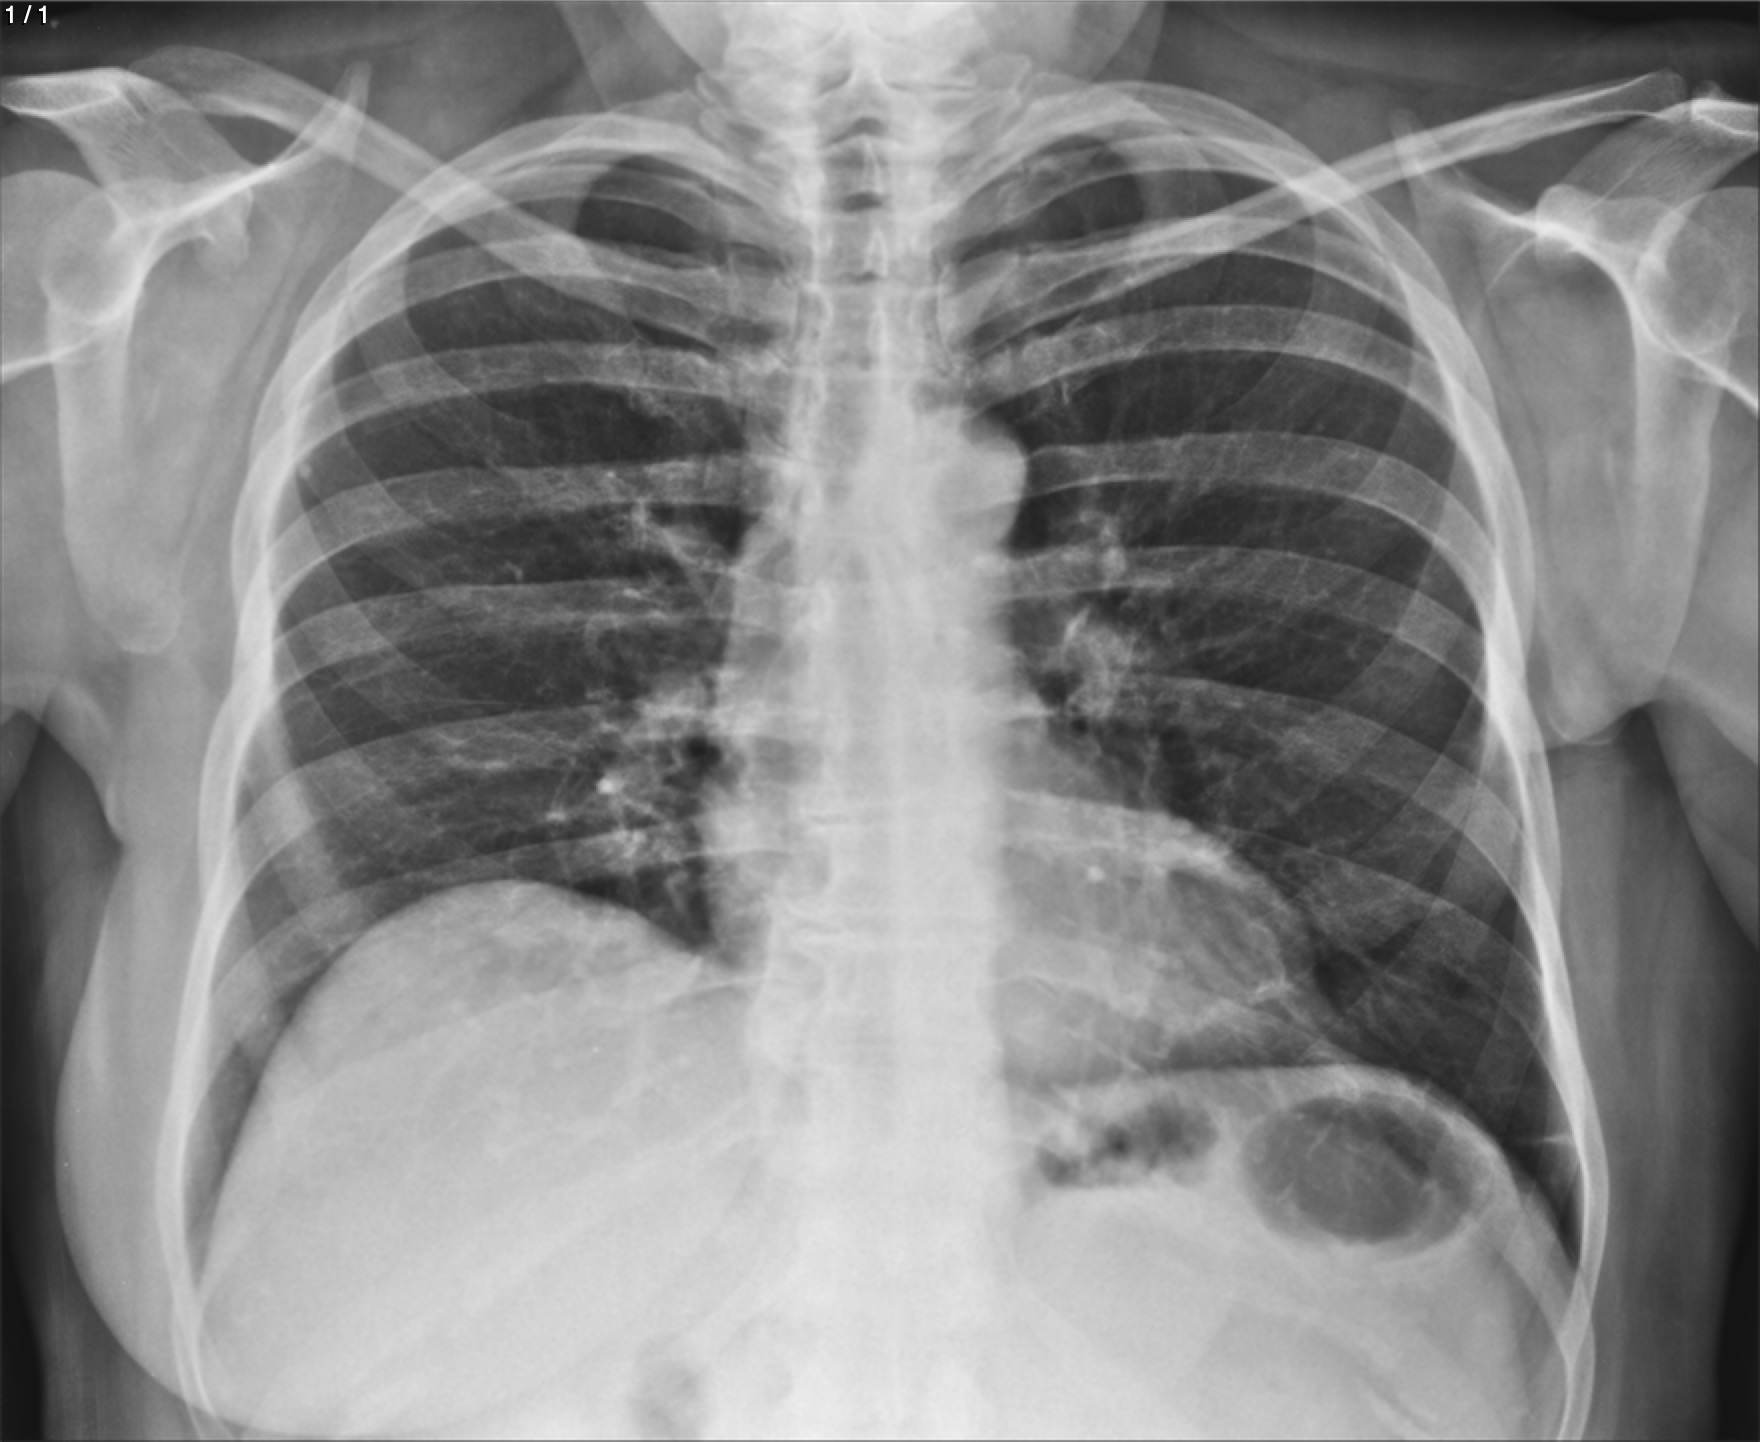

Maria Del Carmen Sanchez - Unnamed